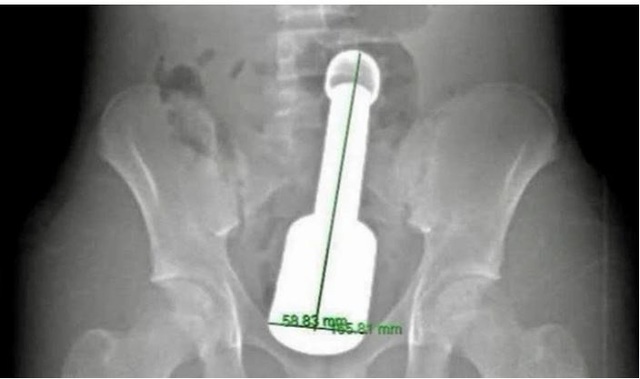

Hình ảnh chiếc chày kim loại dài 18 cm mắc kẹt trong hậu môn thiếu niên 15 tuổi

ẢNH: BỆNH VIỆN ĐA KHOA HÀ ĐÔNG